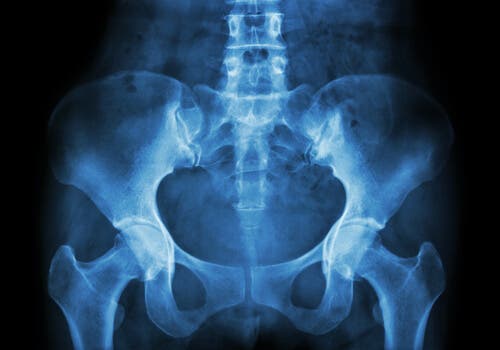

La necrosis avascular es un concepto utilizado para designar el infarto óseo. Lo más frecuente es que aparezca en la articulación de la cadera, en concreto en la inserción de la cabeza del fémur. Por otra parte, también puede encontrarse como necrosis aséptica, isquémica o incluso osteonecrosis.

Por otra parte, tiende a aparecer en la cabeza del fémur. Sin embargo, aparece con menos frecuencia en zonas como el húmero, la mandíbula o la tibia (en la región cercana a la rodilla).

- Obtención de imágenes internas. Se pueden realizar mediante radiografía, gammagrafía ósea, resonancia magnética (o RM), tomografía axial computerizada (o TAC).